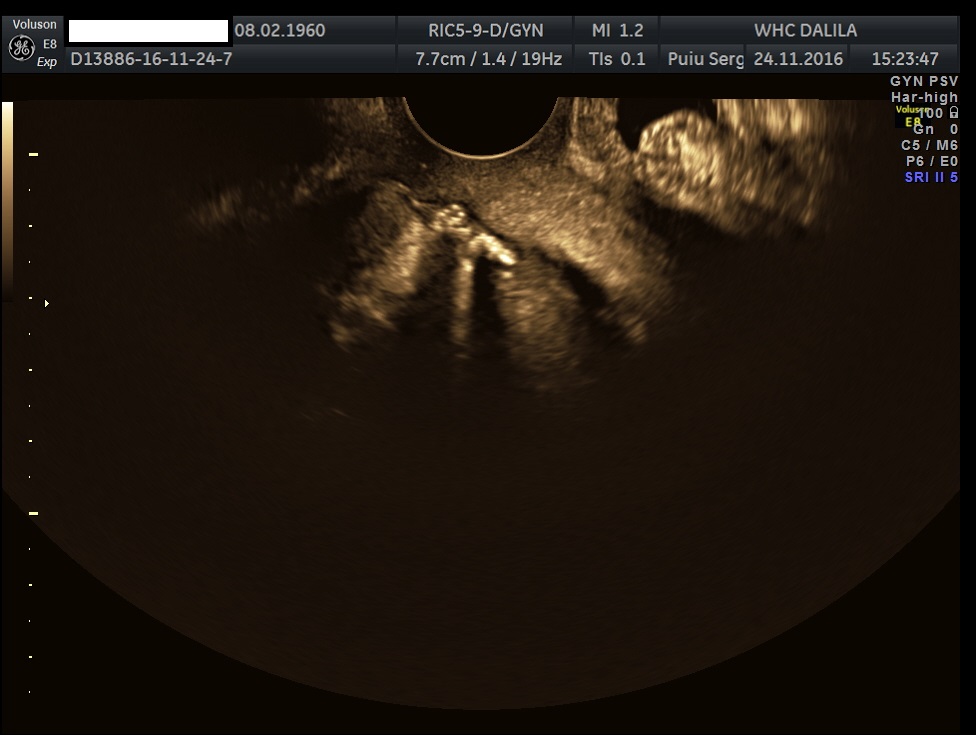

Transvaginal and transabdominal ultrasound scans were performed, which has shown the enlarged uterus with indistinct borders on the left side and a complex mass in left lower abdominal quadrant. A large irregular thick-walled, ill-defined multiloculated cystic/solid lesion with complex fluid collections and peripheral flow on color Doppler were seen. The anatomic distinction between the ovary and the fallopian tube could no longer be identified (Fig. 1). A tubo-ovarian abscess (TOA) was presumed. Endovaginal sonogram showed a dilated uterine cavity and cervical canal, filled with heterogeneous, complex fluid and echogenic masses (Fig. 2a-c). An intrauterine contraceptive was detected. A cavity within myometrium with low-level internal echoes fluid also was revealed (Fig. 2c). This complex adnexal mass was adherent to uterus and a communication between TOA and the cavity within myometrium with fluid-debris level fluid was detected (Fig. 3a-b). This finding presumed a perforation of the TOA into uterus, due to myometrium necrosis, and spontaneous drainages into uterine cavity through myometrium. Increased echogenicity of the pelvic fat and a small amount of free fluid in cul-de sac also were seen. Fluid movements through fistula canal between TOA and uterine cavity were clearly seen when a gently pressure by ultrasound probe was applied (Video 1).

Figures 2a-c. Endovaginal sonograms. Dilated uterine cavity and cervical canal, filled with heterogeneous, complex fluid and masses. An intrauterine contraceptive device also can be easily seen. Note the cavity within myometrium with low level internal echoes fluid and a fluid-fluid level on figure 2c.